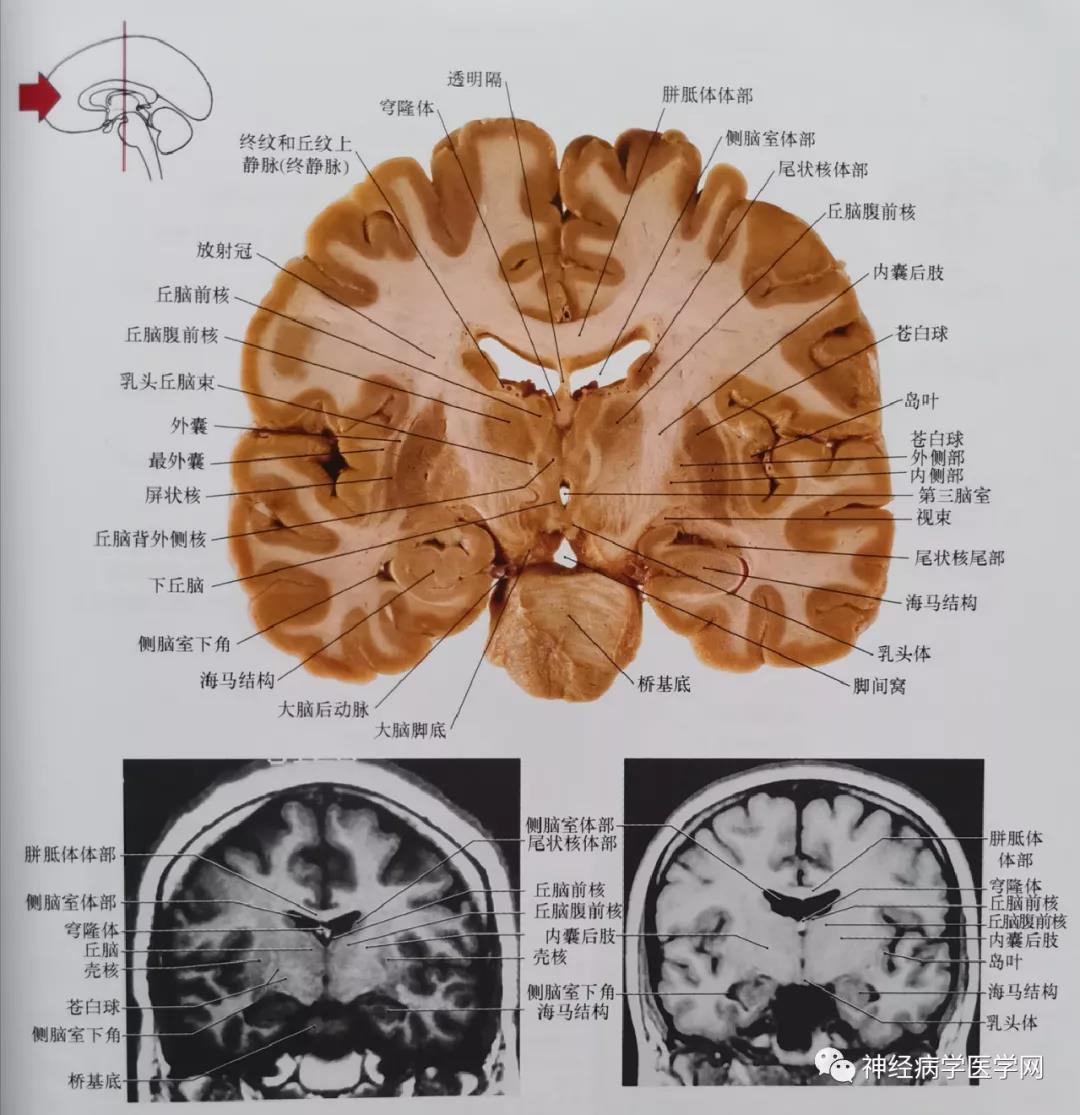

同意

图3 通过丘脑前结节及穹窿柱(前连合尾侧)平面的冠状位影像。此平面也通过内囊膝部。此平面亦包括苍白球的两部分;内侧(内段)部分及外侧(外段)部分。终静脉丘纹上静脉。

海马位于侧脑室颞角的腹内侧面,在磁共振影像中表现出的纹理代表其细胞体部与纤维相交错的层次关系(可参见图4)。另一方面,杏仁核位于颞角的嘴端,影像学中信号均匀一致(如图)。简单总结一下这些结构的关系,即海马为脑室内带有纹理的结,杏仁核表现为位于脑室外的均匀一致的信号。冠状位平面,从一个结构向另一个结构的转换非常迅速。

图4 通过丘脑前核、乳头丘脑束、乳头体平面的冠状位影像。此平面也包括桥基底(切片及磁共振影像可见)。这两张片子为相同平面磁共振影像(均为反转恢复技术),可显示许多切片上确认的解剖结构。苍白球在切片中清晰地分为内、外侧两段。此外,终静脉亦称为丘纹上静脉。